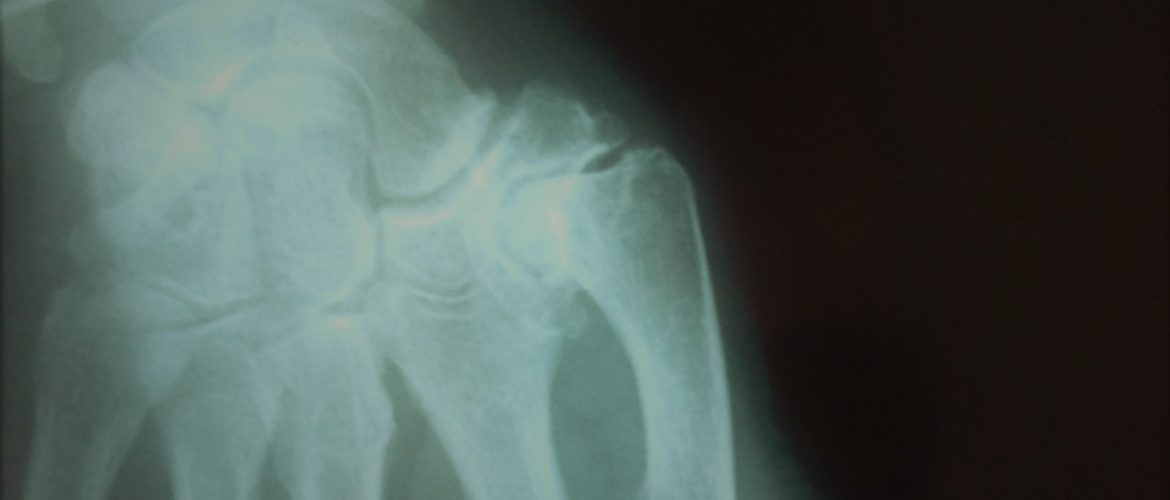

Conforme a doença vai evoluindo o polegar pode ir contraturando-se em adução, isto é, dificuldade em abrir o polegar. A contractura em adução acompanha-se por hiperextensão compensatória da articulação metacarpo-falangica.

Se o polegar atinge esta fase (deformidade em Z) torna-se mais frágil, menos preciso e mais fraco e com maior dificuldade em agarrar grandes objectos.

contractura 1ª metacarpiano e hiperextensão MCF

Rizartrose avançada com contratura do 1º metacarpiano

e hiperextensão MCF